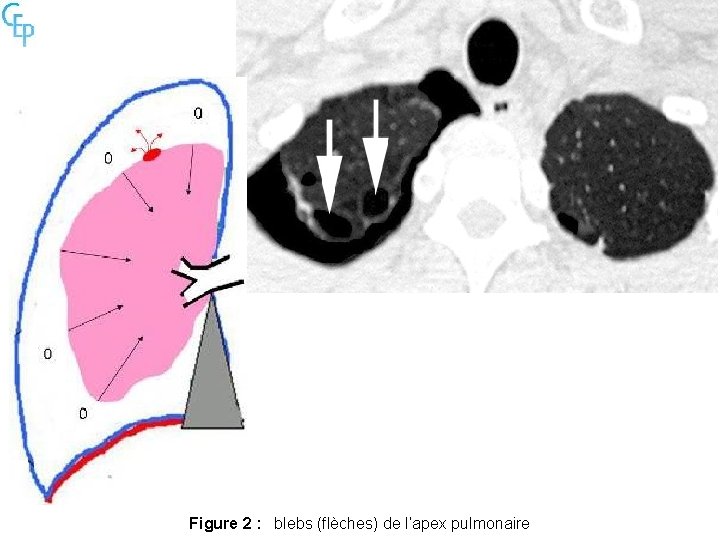

Figure 2 : blebs (flèches) de l’apex pulmonaire